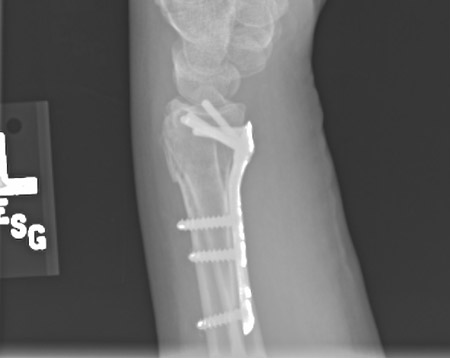

Volar locking plate fixation was found to result in better fracture alignment than closed reduction and cast immobilisation; however, there were no clinically important differences between treatments with respect to patient-reported pain and function at 12 months post-treatment.[62]

Following volar plate fixation, patients can be safely treated with a soft dressing.[63] Some surgeons prefer a cast for pain management. However, this period should not be longer than 3 weeks.[64] Following K-wire fixation, a gauze is placed over the K-wires and a back slab applied. Wires are generally removed 4 to 6 weeks following surgery.

[Figure caption and citation for the preceding image starts]: Plate fixation after open reduction with a volarly placed plate and screwsFrom the collection of Dr Chaitanya S. Mudgal [Citation ends].